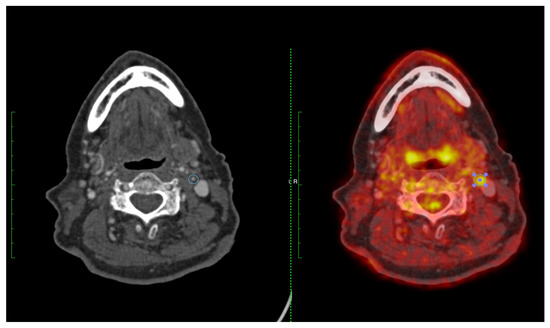

4. Development of FDG-PET Imaging as a Marker of Plaque Vulnerability

- Evans, N.R.; Tarkin, J.M.; Chowdhury, M.M.; Le, E.P.V.; Coughlin, P.A.; Rudd, J.H.F.; Warburton, E.A. Dual-Tracer Positron-Emission Tomography for Identification of Culprit Carotid Plaques and Pathophysiology In Vivo. Circ. Cardiovasc. Imaging 2020, 13, e009539. [Google Scholar] [CrossRef] [PubMed]

- Vesey, A.T.; Jenkins, W.S.; Irkle, A.; Moss, A.; Sng, G.; Forsythe, R.O.; Clark, T.; Roberts, G.; Fletcher, A.; Lucatelli, C.; et al. (18)F-Fluoride and (18)F-Fluorodeoxyglucose Positron Emission Tomography After Transient Ischemic Attack or Minor Ischemic Stroke: Case-Control Study. Circ. Cardiovasc. Imaging 2017, 10, e004976. [Google Scholar] [CrossRef] [PubMed]